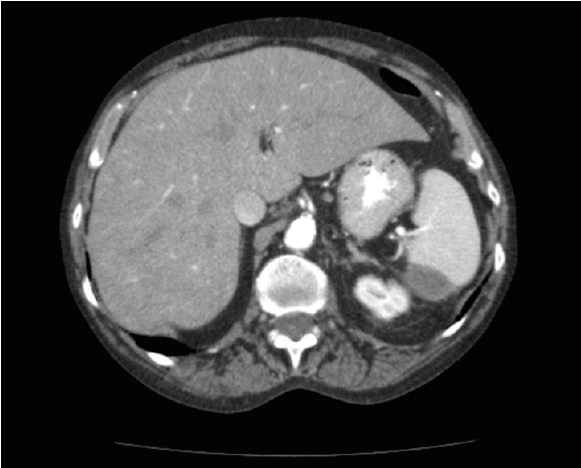

由于持续的腹痛,第一次评估后6小时,外科会诊医生进行了评估。病人报告说四天前做过结肠镜检查,否认以前有外伤。手术小组的评估,发现一个略圆的腹部,腹部有保护,并有肠音。脐周及腹侧未见瘀斑。一项新的对照血液分析显示,6小时内血红蛋白下降了1.3点。重新评估CT扫描后发现脾脏被膜下血肿,无活动性出血迹象(图2)。患者被送入ICU进行密切监测;不需要手术干预。她在重症监护室呆了48小时,需要输血两个单位的红细胞。患者血流动力学保持稳定,疼痛逐渐好转,于6月出院th就在她入院的第二天。出院一个月后随访CT显示血肿明显改善(图3)。

图2:CT扫描显示亚面脾血肿的轴向视图。